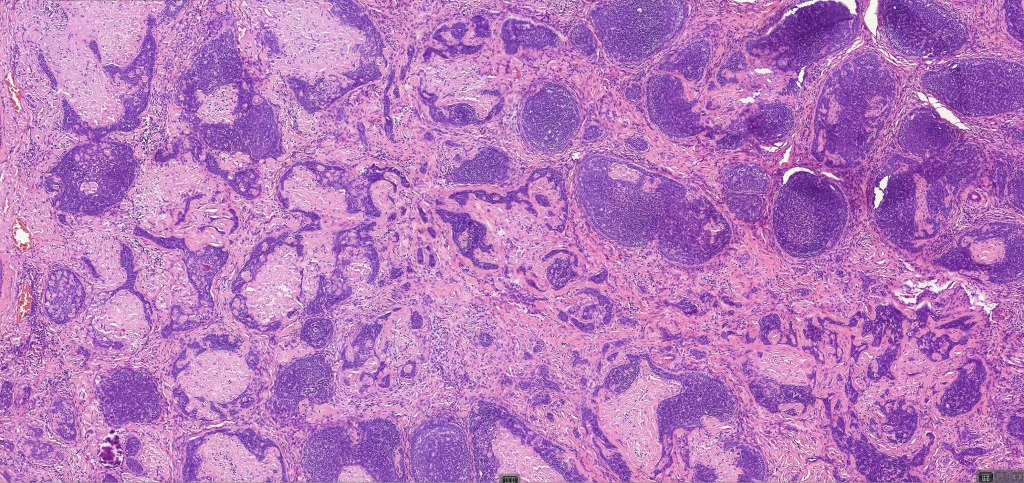

•Sharply circumscribed, unencapsulated nodule in deep dermis +/- subcutaneous fat or deeper (trichoepithelioma is much more superficial)

•Variably sized but generally large, basophilic tumor nodules composed of small uniform basaloid cells with minimal cytoplasm

•Variable keratocysts

•A rich fibromyxoid mesenchymal stroma with variable papillary mesenchymal bodies (sometimes these are absent)